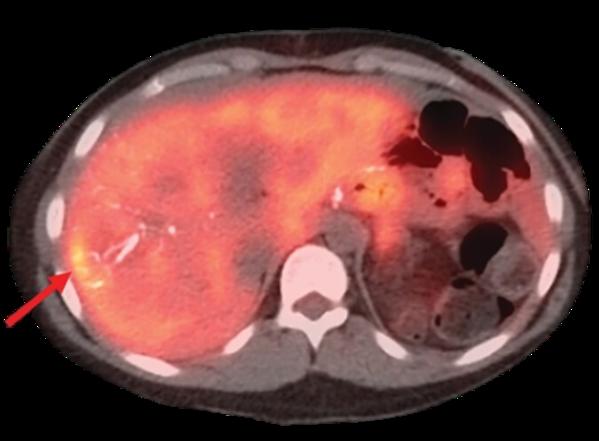

Head and neck cancers affect areas critical to speech, swallowing, and breathing, which makes treatment planning especially important. Detailed imaging, biopsy confirmation, and staging help determine whether surgery, chemotherapy, radiation therapy, or a combination approach will be most effective. Each plan is designed to control the disease while minimizing long-term impact on daily functions.